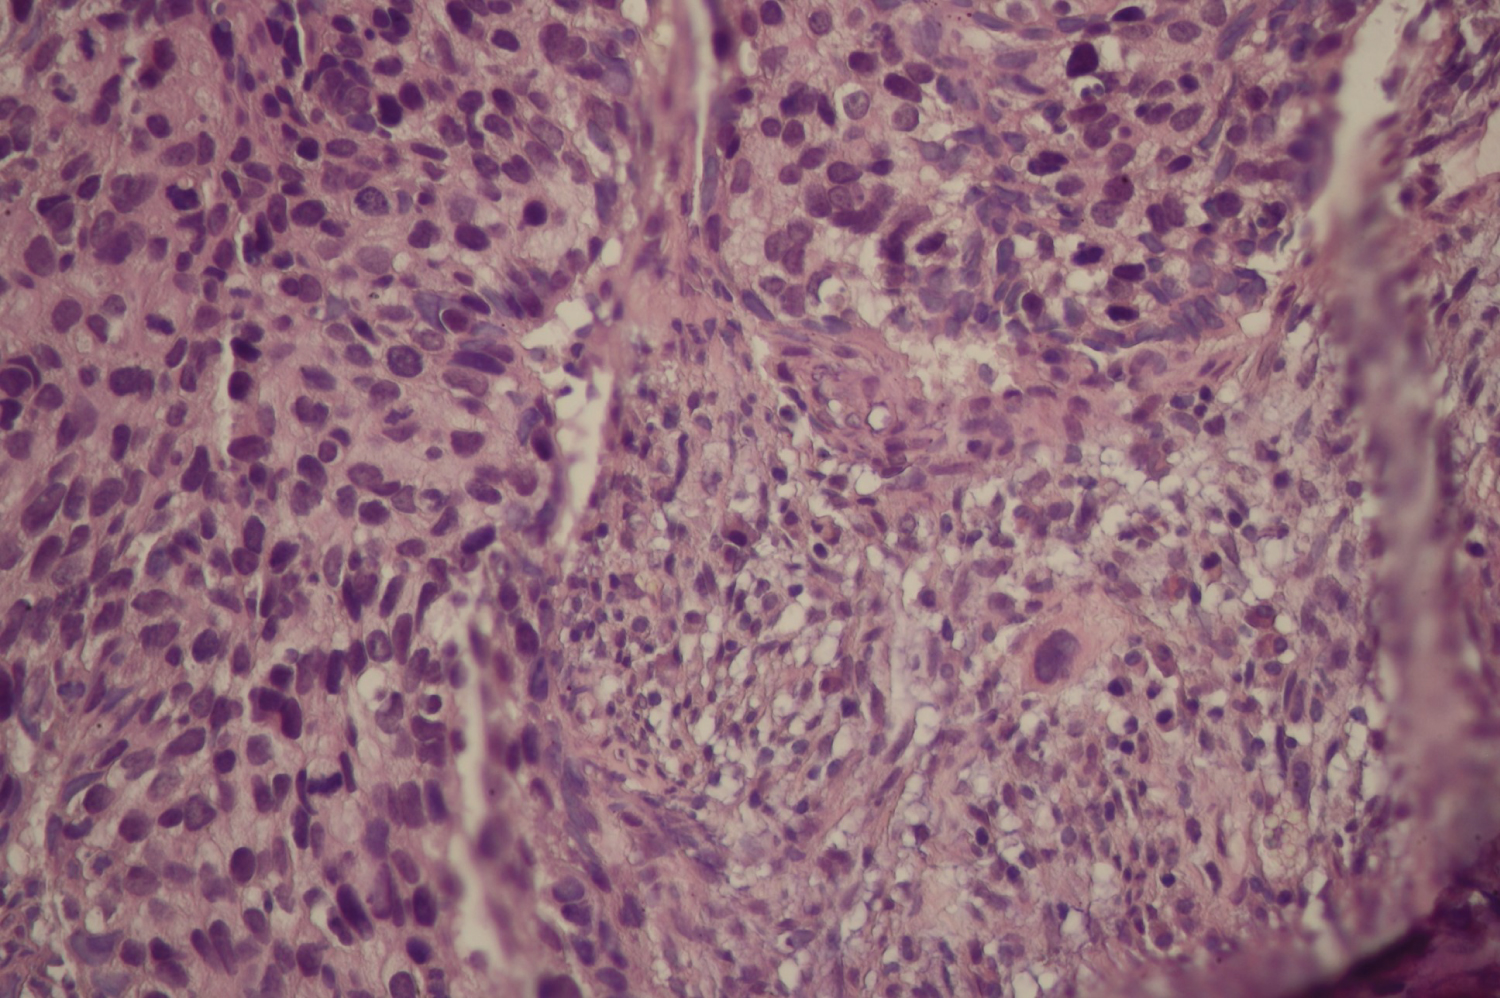

In April 2020, she returned to the WHP clinic at MBH with history of vaginal bleeding for two months. Upon speculum examination, she was found to have a broad, exophytic cervical mass that was friable (Figure 1b). The lesion extended to the distal lower third of the vaginal wall. On recto-vaginal exam, there was bilateral parametrial involvement. Pelvic ultrasound demonstrated a cervical mass and right hydronephrosis. The clinical impression was a 2014 International Federation of Gynaecology and Obstetrics (FIGO) stage IIIB ICC. An ectocervical punch biopsy was performed. The final pathology result confirmed an invasive squamous cell carcinoma of the cervix (Figure 1c). She was then referred for palliative radiotherapy at Douala General Hospital.

Figure 1c: Histological appearance of the cervical cancer of Case One. View Figure 1c